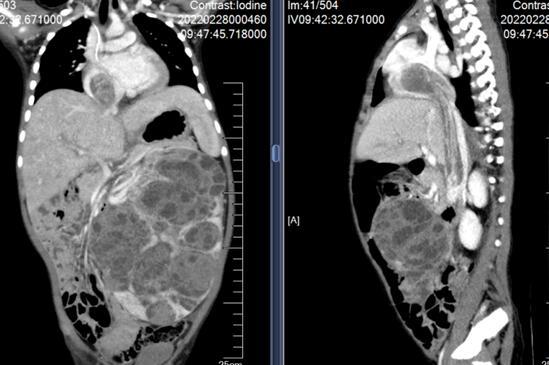

2021年底,家长发现1岁半的阳阳(化名)腹部有包块,至南京市儿童医院就诊。检查结果显示,阳阳的左肾巨大肿瘤,瘤栓从左肾静脉经下腔静脉进入心房。阳阳立即被收入该院肿瘤病区,经过活检确诊为肾母细胞瘤。

肿瘤病区李涛主任医师立即组织了心胸外科、肿瘤科和医学影像科专家进行多学科联合会诊。李涛介绍:“肾母细胞瘤累及范围这么大,非常少见。瘤栓像藤蔓一样,从左肾沿着血管一直向上爬到了心脏,几乎占满了心房。患儿年龄小,肿瘤恶性程度高,手术风险大,不能进行一期手术。只能先为阳阳实施化疗,待肿瘤分期和风险降低后再考虑手术。”

术前,莫绪明针对瘤栓脱落栓塞可导致立刻死亡、下腔静脉段肿瘤剥离极度困难等手术难点,制定了严密的手术方案。手术先由肿瘤病区李涛主任团队进行左肾肿瘤切除、全肝游离暴露全程下腔静脉。再由莫绪明主任手术团队为患儿建立体外循环,让心脏暂时“停工”,阻断肺动脉,打开心脏游离心房瘤栓,采用近远端联合的方式顺利切除了下腔静脉和心房的瘤栓。